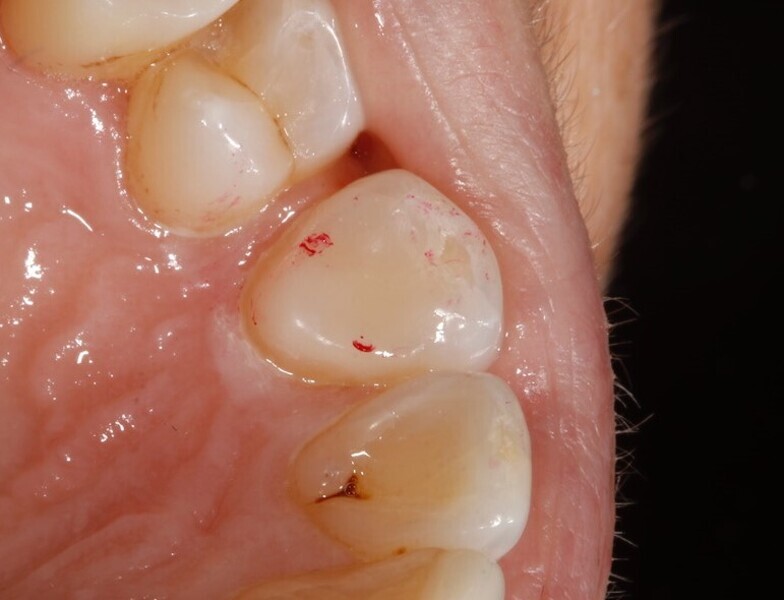

A 48-year-old female patient came to see me in 2004. The patient initially presented because she was unhappy with her two discoloured maxillary central incisors (Fig. 1). She also had chipping and wear of the mandibular teeth and broken posterior bridgework. Her “bite” also felt uncomfortable (Fig. 2).

Fig. 1: 2004—discoloured maxillary central incisors.

Discoloured maxillary central incisors. (All images: Tif Qureshi)